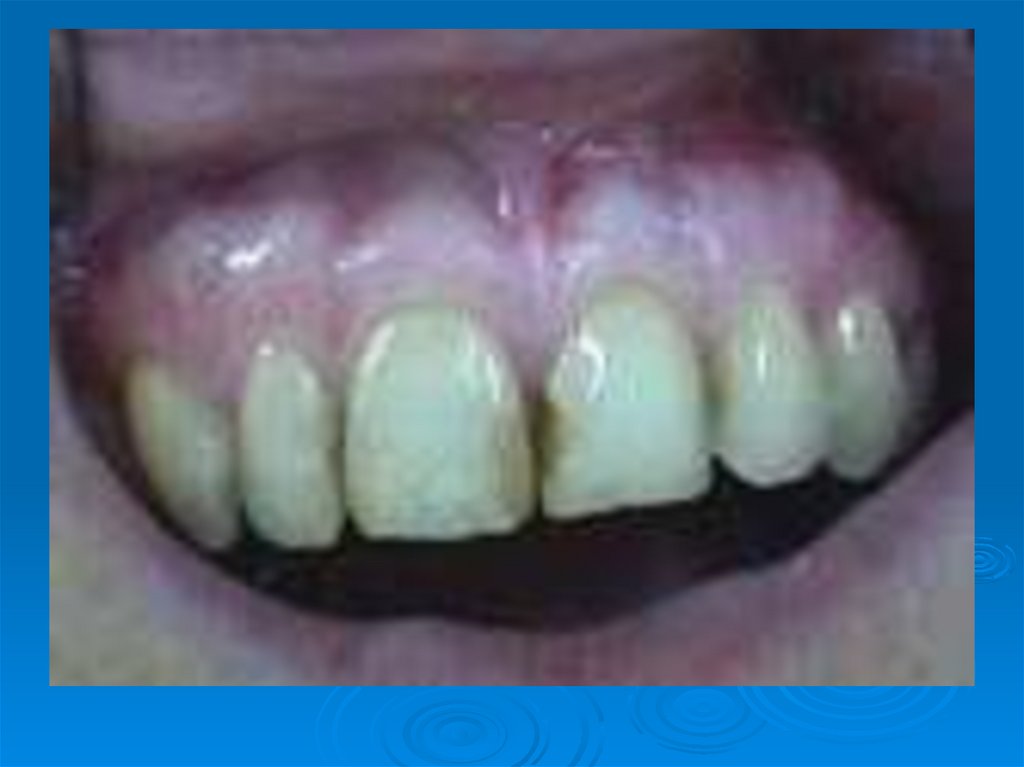

Наличие мягких (мягкий зубной налёт) и обызвествленных (твердый зубной налет – зубной камень)зубных отложений в большой степени

24. Наличие мягких (мягкий зубной налёт) и обызвествленных (твердый зубной налет – зубной камень)зубных отложений в большой степени

зависит от

качества гигиенического ухода

за полостью рта и зубами.